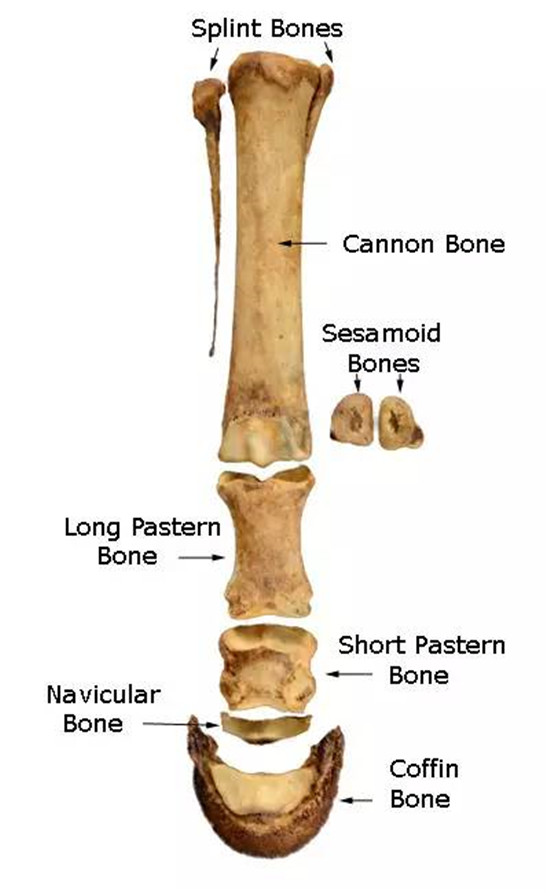

籽骨在哪里?

马一共有12块籽骨,每肢各有3块,分别为2块近端籽骨和1块远端籽骨。近端籽骨位于前后肢球节(Fetlock)掌侧,即第三掌骨和第一指骨的交界掌侧;而远端籽骨则位于冠关节(DIP关节)掌侧。即第二指骨和第三指骨交界掌侧,因远端籽骨外形像一片小舟,因此又称为舟状骨。

术语太专业,二货搞不懂,直接上图!

▲实物对照